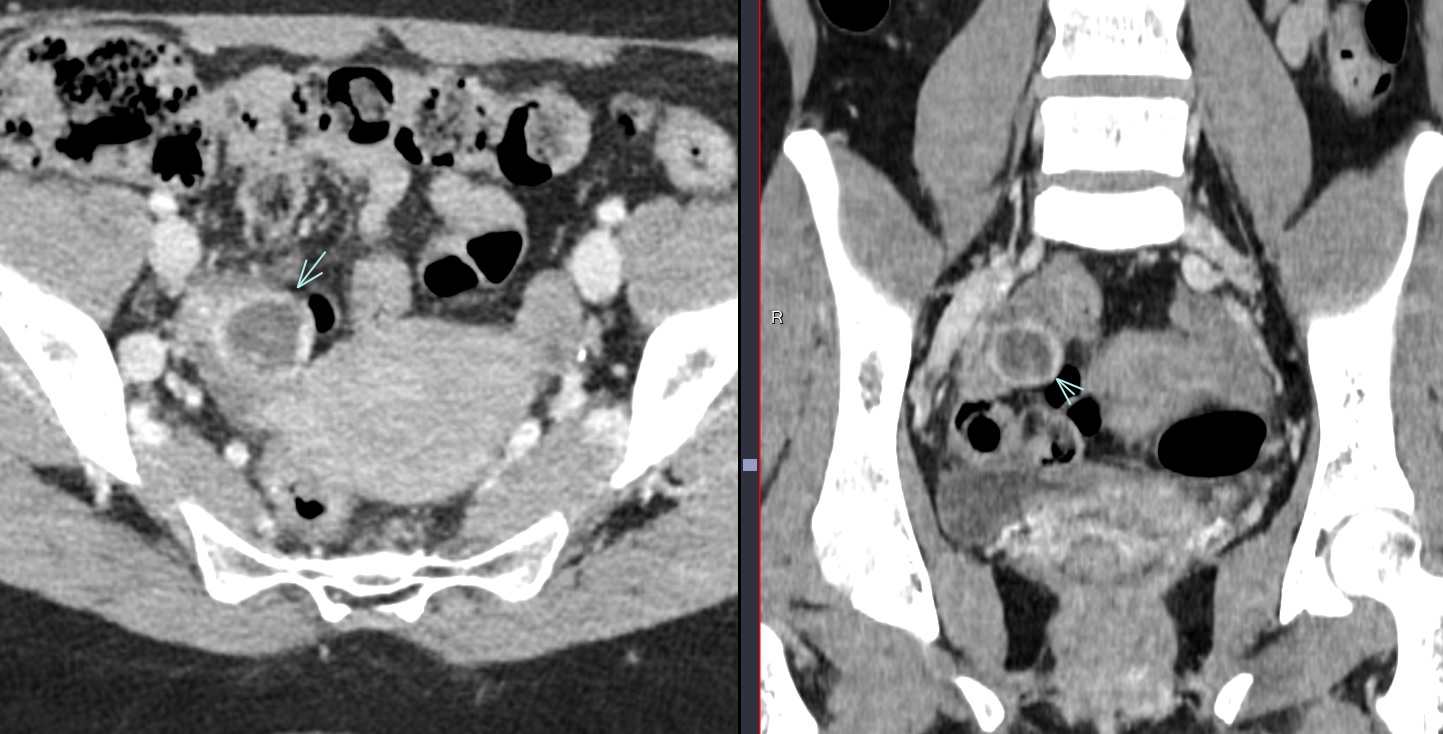

• Aspect en “huitre” avec kyste “vidé” et prise de contraste périphérique (ring of fire)

kyste ovarien corps jaune luteum regles prémenstruel albicans